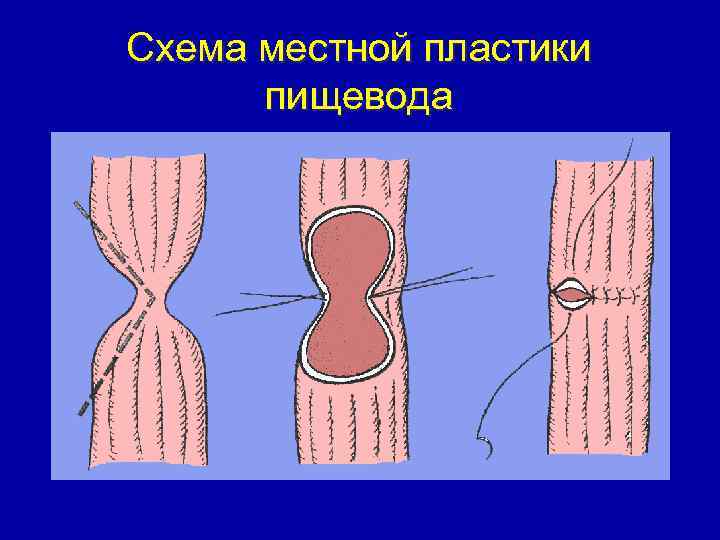

Схема местной пластики пищевода по типу анастомоза в “ 3/4”

Схема местной пластики пищевода